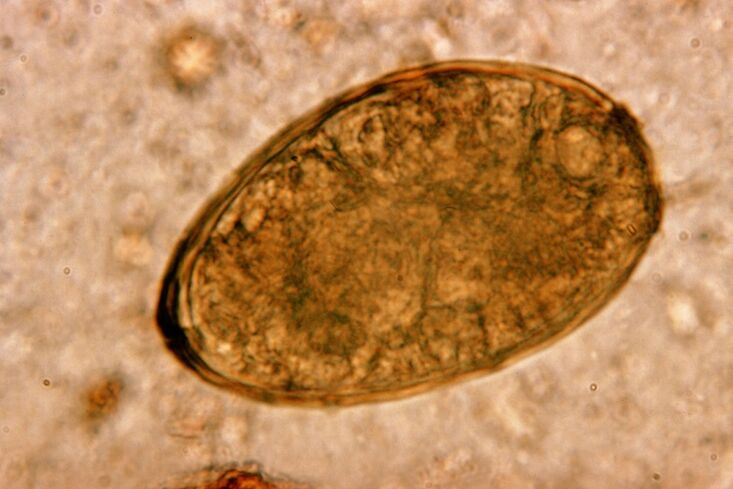

Fluke paru -paru cacing kecil, yang dimiliki oleh kelas trematoda, adalah "khusus" dalam parasit khusus di dalam paru -paru. Ia menyebabkan masalah yang lebih serius dalam sistem pernafasan daripada, contohnya, cacing bulat.

Infiltrat dan pendarahan berlaku di tapak penyetempatan, mewujudkan rongga yang dipenuhi dengan metabolit cacing, parasit mati dan tisu paru -paru. Kerosakan yang disebabkan oleh kebetulan paru-paru dikompaun oleh fakta bahawa ia adalah hati panjang yang boleh hidup di badan tuan rumah sehingga 20 tahun.